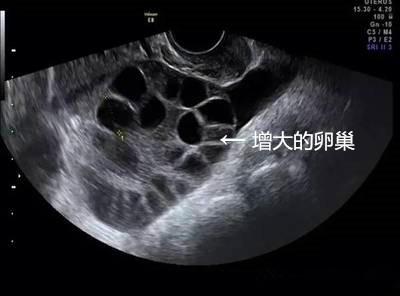

取卵成功后,中介就没有再联系琳琳。但取卵5天后,琳琳出现持续性下腹胀,还有十分明显的胸闷症状。她再次联系卖卵中介,但对方拒绝承担责任,还威胁琳琳不要再纠缠。琳琳到我省这家妇幼保健院就诊,B超提示腹腔内大量积液,胸腔少量积液,卵巢增大超过3倍以上,考虑是卵巢过度刺激综合症,被收治住院。

林医师介绍,女性卵巢每个月都会有一批基础卵泡生长,但其中只有1到2颗会成熟。如果用促排卵针来刺激所有卵泡都成熟,那么卵巢就会变大。卵泡越多,卵巢被撑得越大。尤其是年轻女性,卵巢条件好,基础卵泡多,用高剂量药物促排后,若获卵大于15颗,卵巢过度刺激的风险就大。因此在杭妇院生殖医学中心给不孕不育女性做试管婴儿前,给患者做促排卵也要求少于15颗,正是为了避免女性得卵巢过度刺激综合征。

1、卵巢过度刺激综合征,尤其是瘦小、年轻的女孩子更容易得。卵巢增大导致卵巢壁毛细血管通透性增大,体液积聚于组织间隙,进而使引起腹腔积液、胸腔积液,甚至会导致血栓,危害生命。